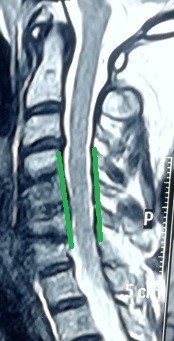

انزلاق غضروفي عنقي متعدد قبل وبعد الجراحة

versatile herniated disc before surgery

An image of an MRI scan of a 47-year-old patient suffering from partial quadriplegia due to multiple cervical disc herniation from the fourth cervical vertebra to the seventh. As shown in red, the location of the slip and the size of the effect resulting from pressure on the cervical spinal cord. And the image shaded in green after a surgical microscope surgery to remove the cartilage from the front and install alternative cervical cages after four months of surgery, as it shows the marrow liberation from pressure, which reflected on the patient's condition improvement.